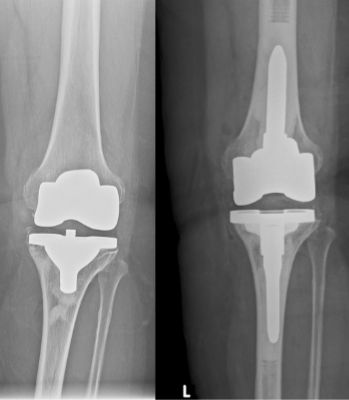

Wechselendoprothetik des Kniegelenks

Keine eingebaute Prothese hält ewig, vielmehr ist die Standzeit der Prothesen begrenzt. Meist liegt sie zwischen 10 bis 15 Jahren. Im Laufe dieser Zeit kommt es infolge von Abriebpartikeln zu einer Entzündungsreaktion, die dazu führt, dass Knochen abgebaut wird, und die Prothese somit aus dem Knochenbett auslockert. Durch diesen Prozess wird der Knochen geschwächt, so dass es bei nachgewiesener Lockerung zu einer zeitnahen Versorgung kommen sollte. Prinzipiell können die Prothesenteile isoliert von einander locker werden (Oberschenkelrollenkomponente oder Schienbeinkopfkomponente), es können aber auch beide Teile (Oberschenkelrollenkomponente und Schienbeinkopfkomponente) von der Lockerung betroffen sein.

Ist die Lockerung allein auf eine Entzündungsreaktion aufgrund des Abriebs zurückzuführen, sind also keine Bakterien vorhanden, dann kann der Wechsel in einer Operation erfolgen und vom Lockerungsgrad der Komponenten abhängig gemacht werden. Hierbei wird dann stets nur der lockere Anteil gewechselt.

In der Orthopädischen Universitätsklinik in Ulm werden jährlich über 50 Prothesenwechsel am Knie durchgeführt. Wir dürfen deshalb von uns behaupten, dass wir über eine große Expertise verfügen. Wie in der Primärendoprothetik halten wir auch für die Wechselsituation ein großes Repertoire an Revisions-, Sonder- und Spezialimplantaten vor, um auf die besondere Situation in der Wechselsituation (große knöcherne Defekte, schlechte Knochenqualität, Knochenbrüche neben dem Implantatlager) reagieren zu können. Hierdurch ist gewährleistet, die biologische Situation des Gelenkes erneut möglichst gut zu rekonstruieren.

Wird während Ihres Besuches bei uns in der Ambulanz durch das persönliche Gespräch mit dem Arzt, die körperliche Untersuchung und anhand der Röntgenaufnahmen eine Prothesenlockerung festgestellt, so wird in der Regel am gleichen Tag eine Punktion des betroffenen Gelenkes durchgeführt. Die anschließende mikrobiologische Untersuchung des gewonnenen Materials versucht, Bakterien nachzuweisen. Um ganz sicher zu gehen, dass keine Keime „übersehen“ werden, wird das Material 14 Tage „bebrütet“. Das endgültige Ergebnis steht also erst nach 14 Tagen fest. Zu diesem Zeitpunkt wird das weitere Vorgehen (einzeitiger oder zweizeitiger Wechsel) festgelegt und mit Ihnen besprochen.